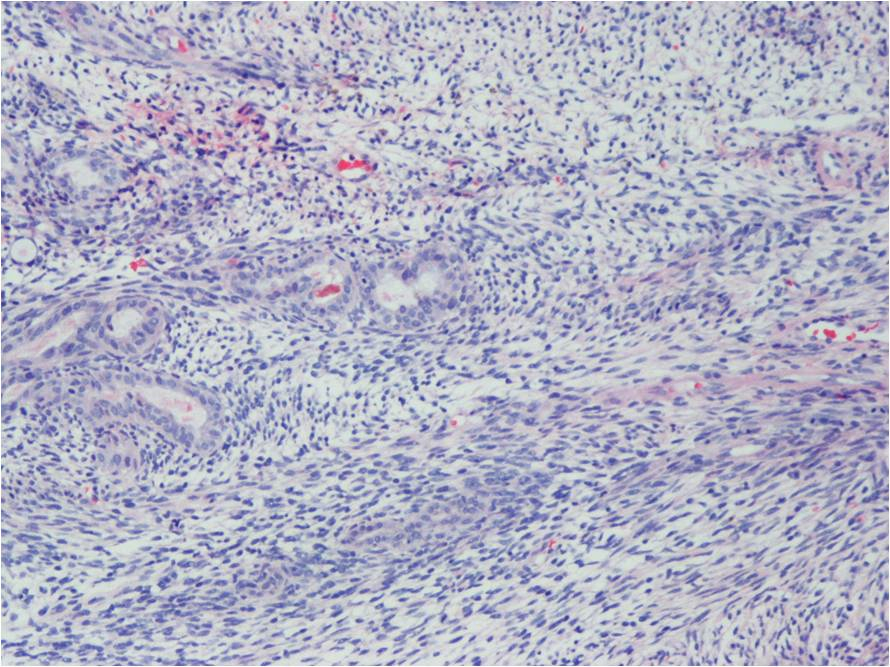

Microscopic Pathology

Synovial Sarcoma is composed of two different cell types

Spindle cell (small, uniform, and ovoid cells with pale nuclei and the cytoplasm is sparse)

Epitheloid cell (ovoid nuclei and abundant cytoplasm)

Biphasic form is composed of both epithelial-cell and spindle-cell components in equal proportions (Fig. 6-8)

Monophasic Fibrous type predominantly spindle cell.

Monophasic Epithelial type is difficult to differentiate from adenocarcinoma without cytogenetics and immunohistochemistry.

Poorly differentiated type demonstrates features of high grade small round cell tumor with dense cellularity, numerous mitotic figures, and areas of necrosis.

Inmunohistochemical profile: Vimentin (+), Cytokeratin (+), Epithelial Membrane Antigen EMA (+)